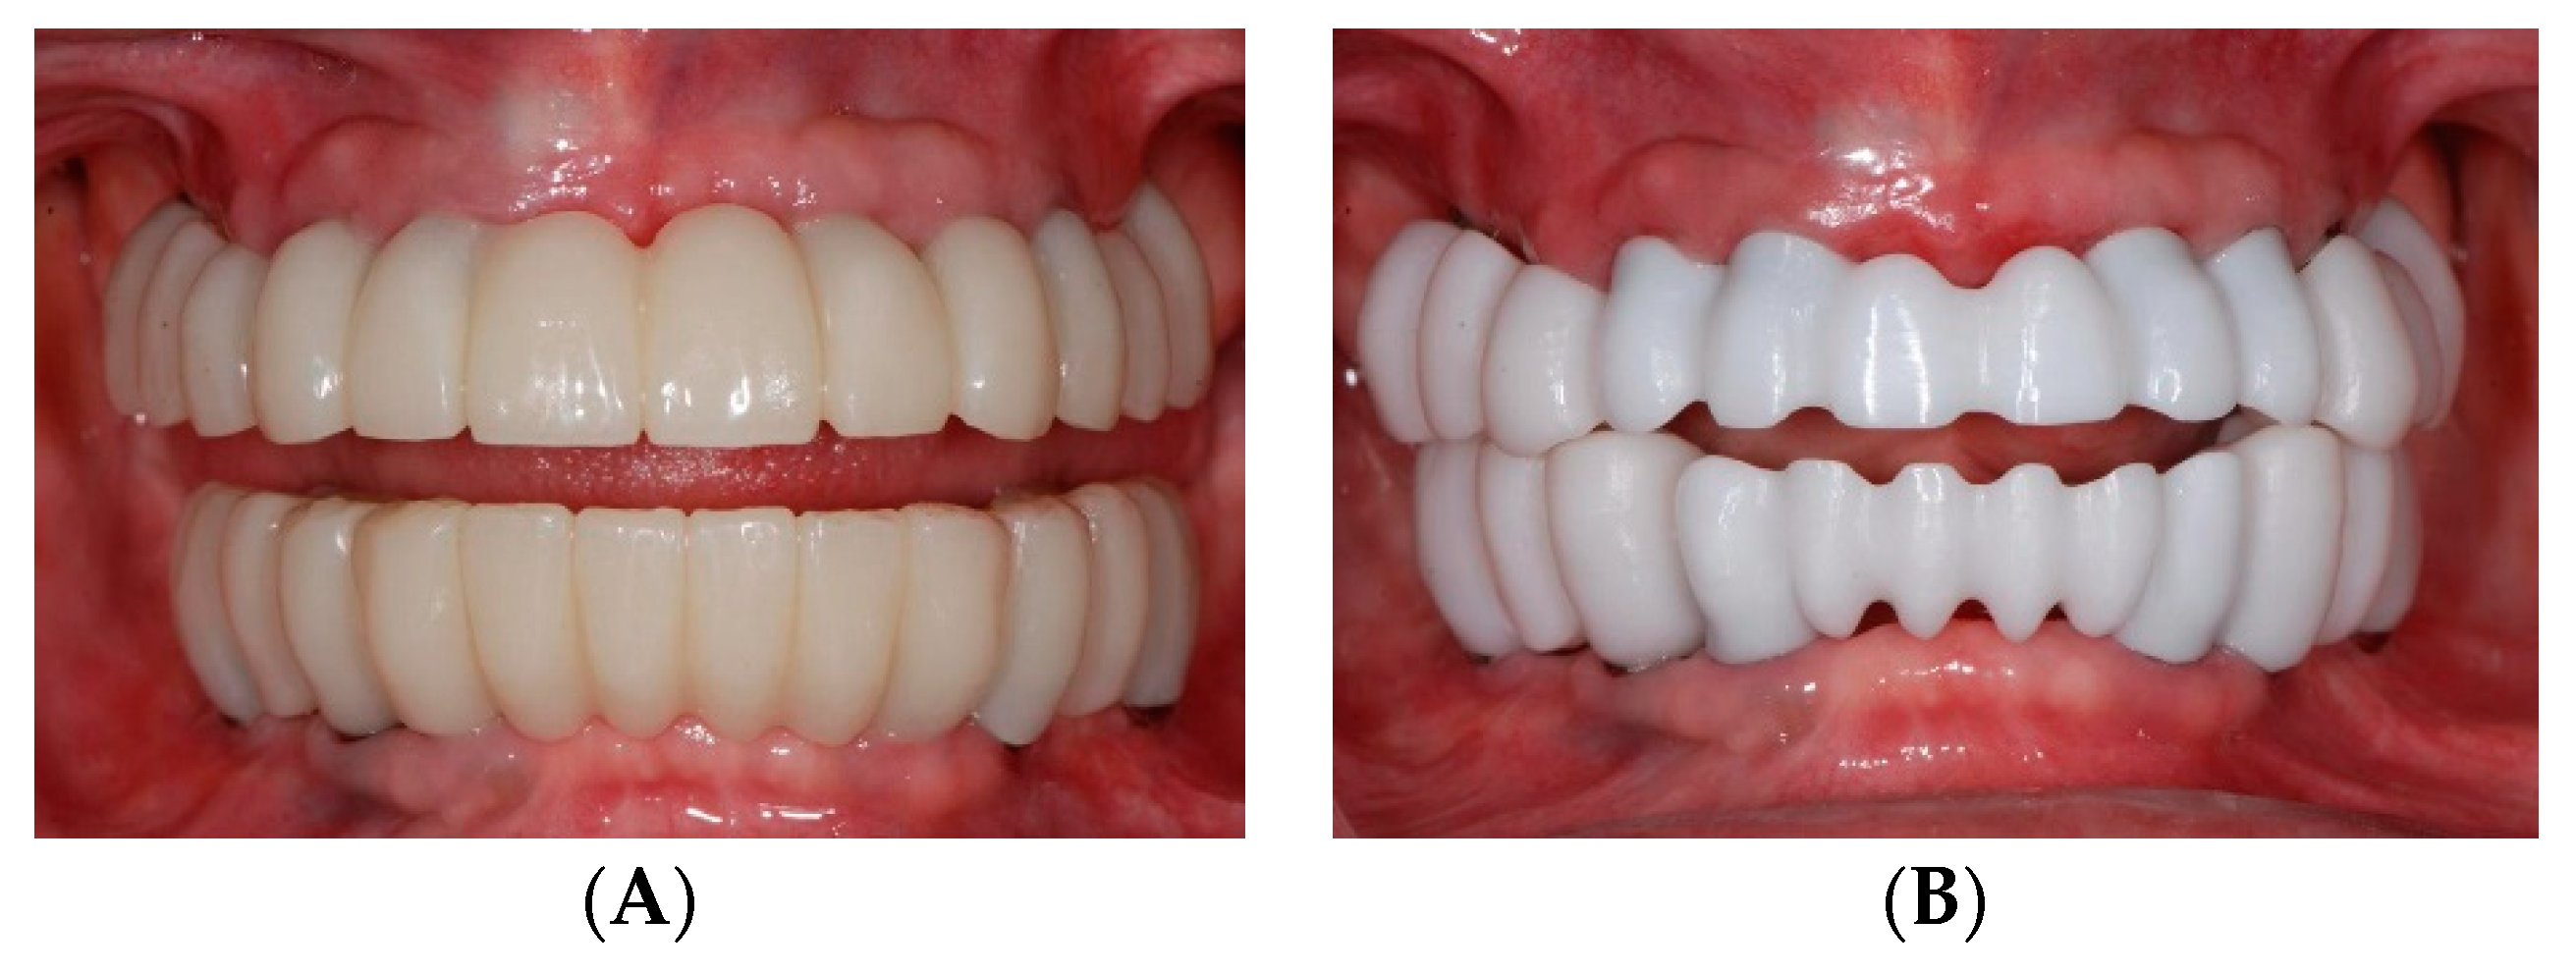

2.4. Restorative Phase: Second Strategic Extraction and Conversion of Provisional Prostheses with Integrated Digital Workflow

3. Discussion